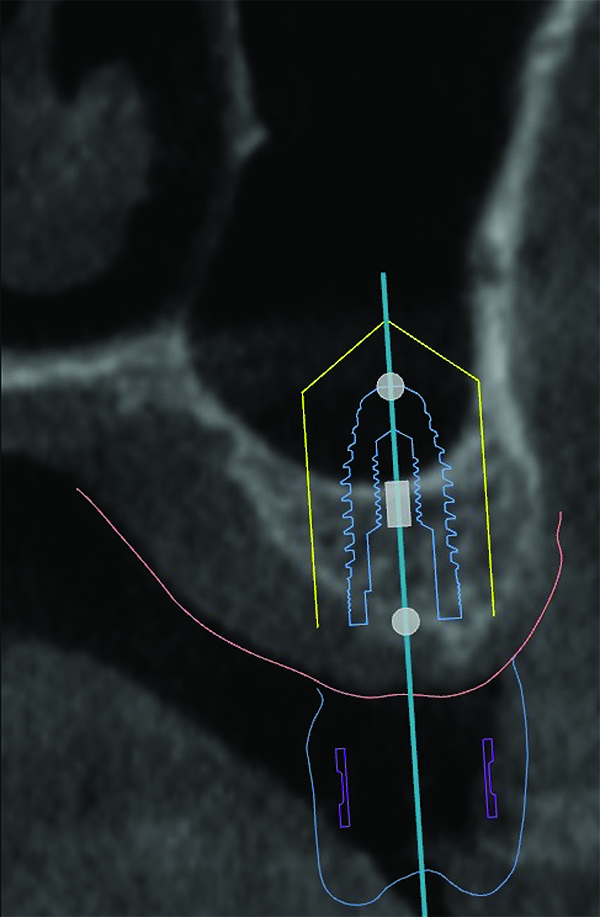

3D radiographic files (CT, CBCT) are stored digitally using a standardized digital imaging and communication in medicine (DICOM) format. In combination with a radiographic guide fabricated from a diagnostic wax-up, CBCT can be used to plan implant location and angulation based on prosthetically driven parameters and local bone/tissue constraints (Figure 8 through Figure 11). Currently, there are two different protocols to incorporate the radiographic guide in 3D scans and to perform computer guided surgery. The first is the double scan protocol, in which the patient wearing the radiographic guide and the radiographic guide alone are scanned separately. Fiduciary markers incorporated in the radiographic guide allow for matching of the two scans. This protocol allows for digitization of the surgical guide with great accuracy, irrespective of errors introduced by patient scans.18 Specialized software can be used to create a surgical guide (Figure 12).

The second protocol is the single scan protocol. In this protocol, the patient is scanned once while wearing the radiographic guide. Imaging files can be imported to the implant planning software without the need for further processing. As with the double scan protocol, the location and position of implants can be planned and a surgical guide can be fabricated based on the virtual plan.

3D radiographic scans obtained using the single scan protocol can be combined with digital mock-ups performed on intraoral optical scans or scans of casts,20 using the existing natural teeth as fiduciary markers. Different masks for bone, teeth, gingiva, and implants can be designated and processed (Figure 13 and Figure 14). This technology allows for greater accuracy, since implant position will be determined based on natural teeth (fiduciary markers) that are likely to be more stable and accurate than fiduciary markers placed on a radiographic guide.

Regardless of the scanning protocol used, digital advances in 3D imaging, optical scanning, and processing software endow the dentist with unprecedented tools to visualize and examine orofacial structures in 3D. This translates into better diagnosis and treatment planning. By evaluating soft tissue dimensions and contours, bone dimensions and quality, and the location of nerves and vital structures, the dentist can virtually plan implant placement surgery. Indeed, common to all scanning protocols discussed above, the resulting surgical guide reproduces the virtual implant position accurately and without allowing for intraoperative modification of implant position. The dentist can also execute this virtual plan with great accuracy, which is likely to ensure a favorable treatment outcome.

(8) The use of CBCT and digital software for implant treatment planning. The radiographic guide in combination with a 3D CBCT was used to help plan implant position and location.

Figure 8

(9) The use of CBCT and digital software for implant treatment planning. The radiographic guide in combination with a 3D CBCT was used to help plan implant position and location.

Figure 9

(10) The use of CBCT and digital software for implant treatment planning. The radiographic guide in combination with a 3D CBCT was used to help plan implant position and location.

Figure 10

(11) The use of CBCT and digital software for implant treatment planning. The radiographic guide in combination with a 3D CBCT was used to help plan implant position and location.

Figure 11